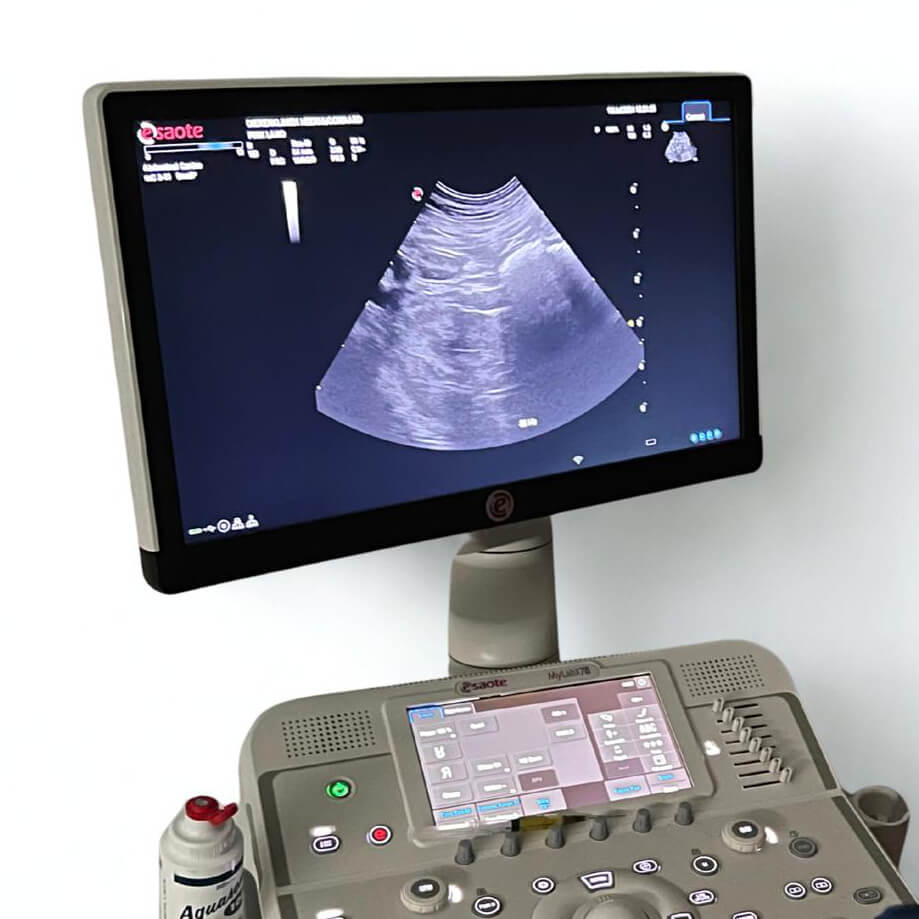

- Moderne apparatuur: we beschikken over recente hoogwaardige echo apparatuur, zodat beeldkwaliteit en diagnostische mogelijkheden optimaal zijn.

Wij bieden geavanceerde echografie aan om uw huisdier grondig en deskundig te onderzoeken. Of het nu gaat om echo van de buik (abdomen) of het hart (cardiologie): met onze moderne apparaten én deskundige dierenartsen zorgen wij voor een betrouwbare diagnose, zodat we tijdig de juiste behandeling kunnen inzetten.